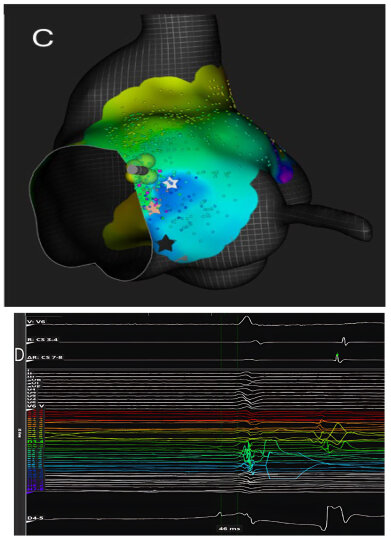

Figure 3. Panel (A). Three-dimensional electroanatomical reconstruction of Koch’s triangle showing the spatial localization of the compact atrioventricular node (white star) immediately inferior to the His bundle region. The red star indicates the coronary sinus. Panel (B). High-fidelity intracardiac recording obtained with a high-density mapping catheter using bipolar filtering (0.1–250 Hz). The electrogram at the ablation site (bottom trace) exhibits the characteristic features of the compact AV nodal potential: a long-duration, low-frequency, low-amplitude “hump” deflection occurring between the atrial and His potentials (white arrow). This signal, confined to the mid- and posteroseptal portions of Koch’s triangle, precedes the onset of the His deflection and disappears outside this region, confirming its origin from the compact AV node. The simultaneous color-coded activation map demonstrates the anatomical relationship between the nodal electrogram and the surrounding structures, guiding precise lesion delivery while preserving distal conduction.